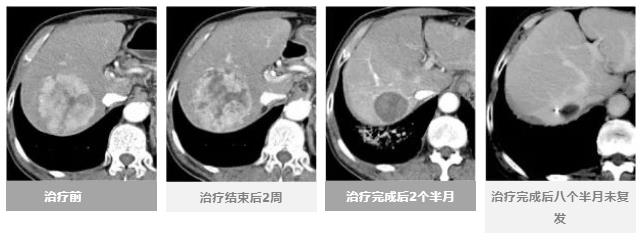

治療效果進度